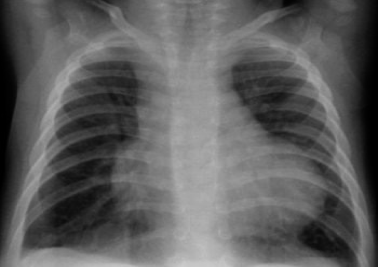

Signs of ASD

- Parasternal heave (RVH)

- Signs of congestive heart failure